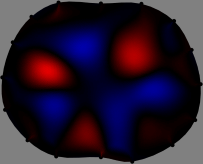

To explain the FER method, we closely examine the correlations among column vectors of the sensitivity matrix , described in Fig. 2. The correlation between and can be expressed as

for [23]. This shows that the column vector is like an EEG (electroencephalography) data induced by dipole sources with directions at locations . Given that two dipole sources at distant locations produce mutually independent data, the correlation between and decreases with the distance between and . Fig. 2 shows a few images of the correlation as a function of for four different positions . The correlation decreases rapidly as the distance increases. In the green regions where the correlation is almost zero, is nearly orthogonal to .

Fig. 2 shows that if and are far from each other, the corresponding columns of the sensitivity matrix are nearly orthogonal. This somewhat orthogonal structure of the sensitivity matrix motivates an algebraic formula that directly computes the local ensemble average of conductivity changes at each point using the inner product between changes in the data and a scaled sensitivity vector at that point: